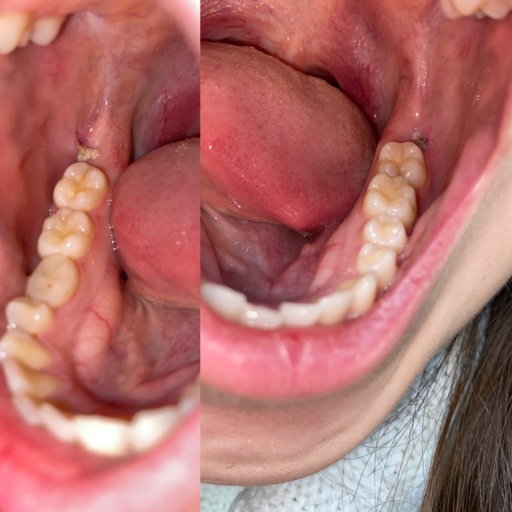

Number 30 molar

This tooth has had a root canal and a crown installed several yrs, ago. Now my dentist says the ex ray shows that the root has now separated and one side broke, therefore the tooth should be removed. Is that correct? I would then have to get a bridge or implant, or just have an empty space. I have all my other teeth except the 4 wisdom teeth. I don't like this situation. Any other possibility?